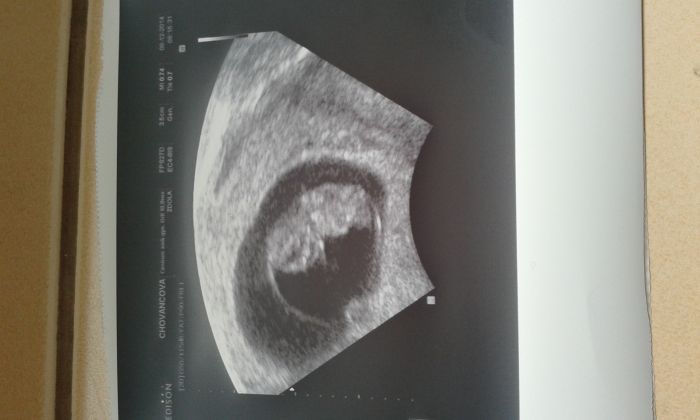

Ahoooj holky,jste zlaté,že jste na mě tak myslely a měly starost.Chtěla jsem se dát výsledek ko,ale když jsem vas otevřela,byla tu dost pošmurná nálada a mě přišlo blbé a nepříjemné jsem dávat své štěstí,když vy se tak trápípete.Omlouvám se. Ale jak už napsala Čiča...prdolka je v pořádku,srdíčko opět krásně tlouklo,měří 1,8 cm.Dostala jsem průkazku a příšti ko až 5.1. včetně odběrů a NT screeningu.

Žirafko moc krásný zprávy a Krásná fotka prdolky. Holky Já to nevydržela a udělala si test. To je Tim ze byl doma a hrozne mě to lákalo :-) byl tam doušek ale ještě uvidím a další test udělám až o víkendu a někam ho schovám ať mě to neláká. :-) na toto mam slabou vůli a jak mám doma test tak mi to nikdy nedá. :-)

Mončo naopak dobré zprávy tu jsou vždycky vítány. Je to krásné, že prospívá mimi, jen tak dál.